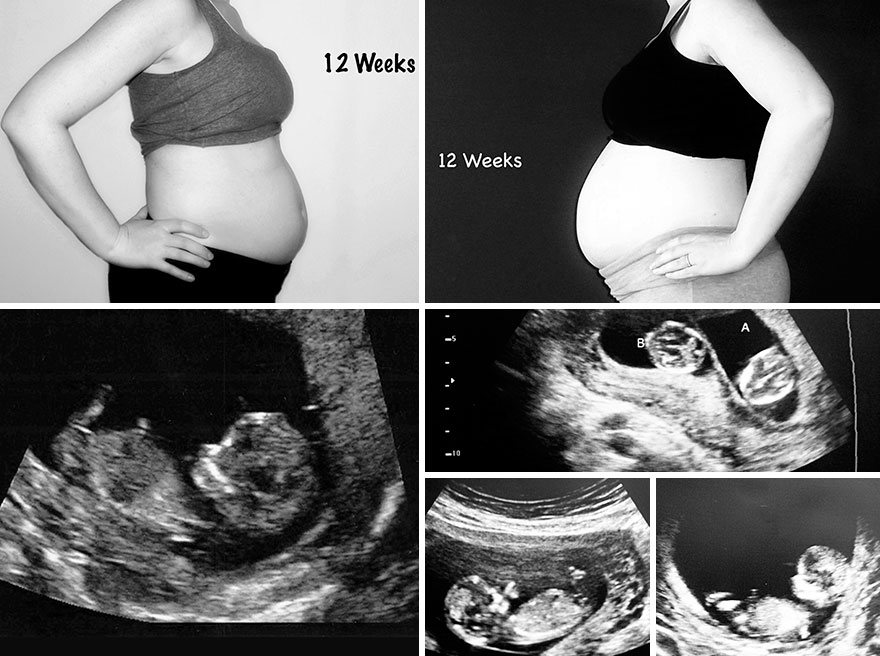

These pictures show the difference in my belly size with my singleton pregnancy and my twin pregnancy. It also shows the week’s corresponding ultrasound pictures. My husband and I continue to be amazed by all we’ve been through to get the amazing kids we have today. Even with the heartache and stress, I would not change a thing. Our three kids, now five years old (singleton) and two and a half (twins) are my world and are truly miracles that would never have been if not for the amazing advances of reproductive medicine. For that, we are truly thankful.

Twelve weeks pregnant – Singleton (left) / Twins (right)